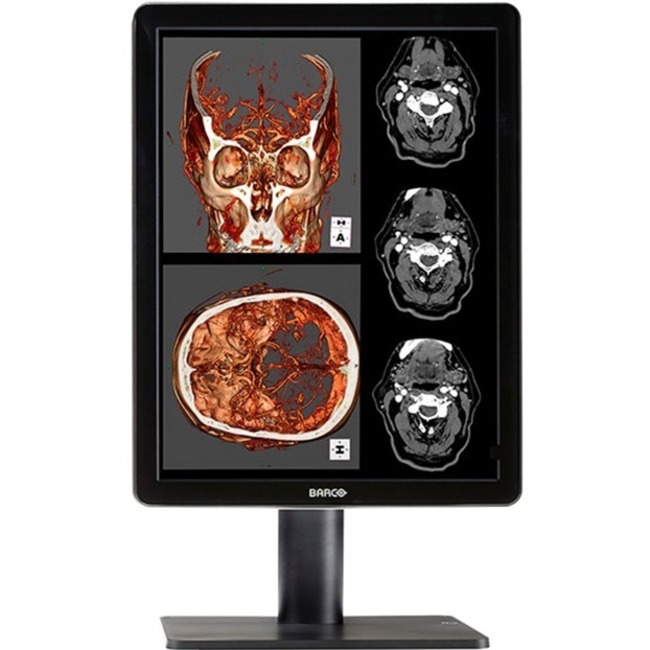

Barco Nio Color MDNC-2221 UXGA LCD Monitor - 4:3

| Product Name | Nio Color 2MP LED (MDNC-2221) |

| Marketing Information | Nio Color 2MP LED is a 2 MegaPixel color display system with LED backlights, providing excellent image quality for confident diagnoses. Nio Color 2MP LED provides an effective display solution for a multitude of applications and modalities, including 3D PACS, 3D echo, ultrasound, orthopedic imaging, CAD, image fusion, nuclear medicine and PET. |

| Product Type | LCD Monitor |

| Viewable Screen Size | 21.3" |

| Maximum Resolution | 1600 x 1200 |